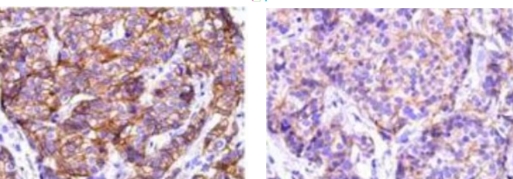

Typical example: CEA staining of paraffin-embedded human colon cancer tissue sections:

When the primary antibody was incubated overnight at 4°C, strong cytoplasmic positivity in cancer cells was observed with a clean background;

When incubated at 37°C for 60 minutes, moderate cytoplasmic positivity in cancer cells was noted with a clean background.

Conclusion: Incubation conditions have a slight impact on staining results, and it is necessary to screen for appropriate incubation conditions.

Typical Example:CD34 staining of paraffin-embedded human placental tissue sections:

HRP-directly labeled secondary antibody: Weak positive staining with low background;

Polymer enzyme-labeled secondary antibody: Strong positive staining with clean background and distinct contrast.

Conclusion: Different chromogenic systems yield distinct chromogenic results. Polymer enzyme-labeled secondary antibodies demonstrate higher sensitivity, cleaner background, and more distinct contrast compared to conventional HRP-directly labeled secondary antibodies.